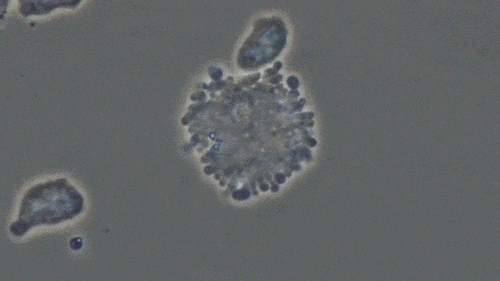

图解:NK细胞消灭癌细胞的过程